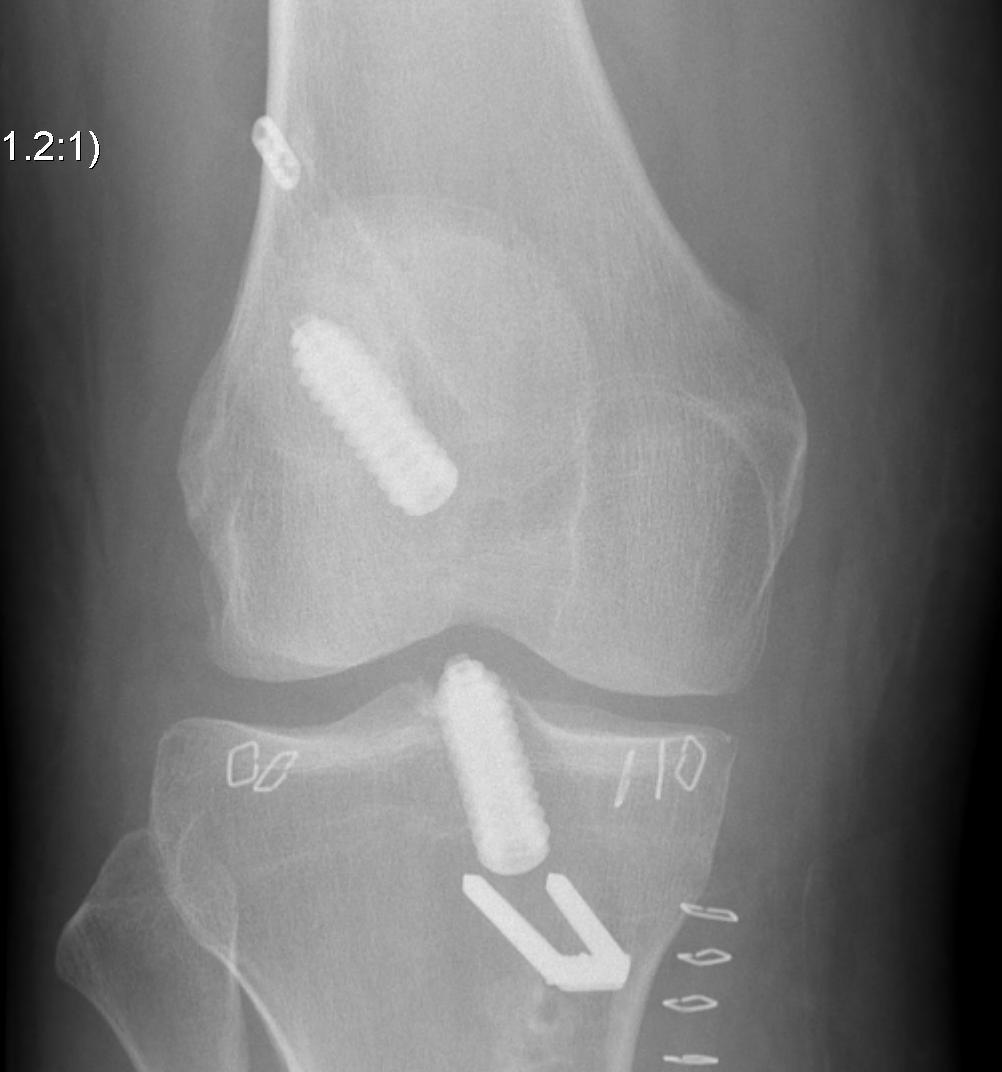

Patient with traumatic failure ACL, previous hamstring with endobutton and bioabsorbable screw

Graft likely too vertical, evidence of tibial tunnel lysis

Achilles allograft used, and 12 mm x 20 mm bone plug used in femoral side. Both tunnels drilled where indicated.

Tibial screw ignored, old femoral tunnel ignored. 12 mm tunnels drilled.

Old staple had to be removed. Graft passed and fixed on femoral side with 9 x 25 mm screw.

Achilles tendon fixed on tibial side with 9 x 25 screw

Tibial bone very poor and screw little bite (advanced very easily too far into tibia, but not seen in joint).

New staple used, but had to be repositioned as cortical bone soft and fracture easily.